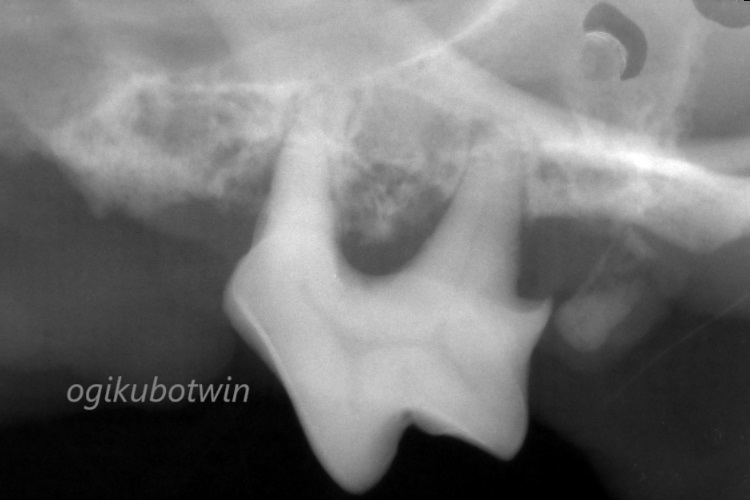

歯の根っこの周囲には歯を支える骨が無くなっており、歯周病が重度に進行している事が確認されました。